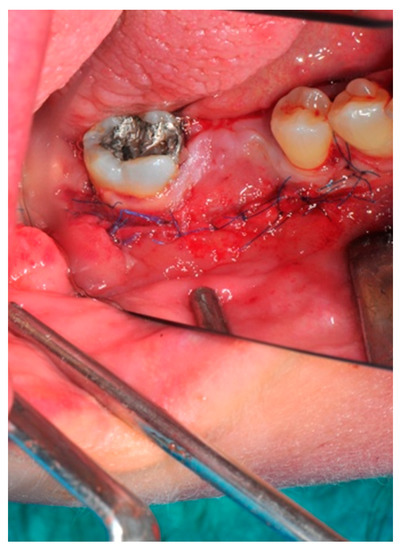

- Suture: Perfect closure is achieved with a first line of horizontal mattress sutures positioned 5 mm from the incision line and, subsequently, with single interrupted stitches connecting the edges of the flap. With this technique, the edges of the flap are reversed, putting the inner layers of the connective tissue in close contact with each other. The intimate connection between the layers of connective tissue forms a barrier that largely prevents the exposure of the membrane (Figure 12 and Figure 13).